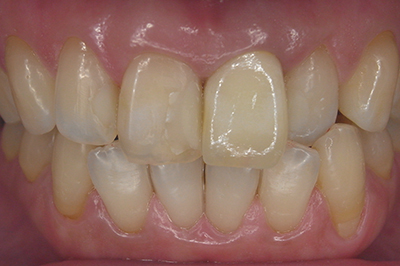

治療例2

歯ぐきが安定した状態

土台をたてた

噛める機能を回復

| ご費用 | 手術費用人工歯根 1本275,000円(税込) 上部構造 88,000円~110,000円(税込) |

|---|---|

| リスク・副作用 | 保険非適応(自費診療) 特定の全身疾患や持病のある方、顎骨密度の足りない方、妊娠中の方は手術ができない場合があります。 下顎のインプラント手術の際、偶発症のリスクがあります。 人工歯根が顎骨と癒着しないリスクがあります。 インプラント周囲炎になるリスクがあります。 |